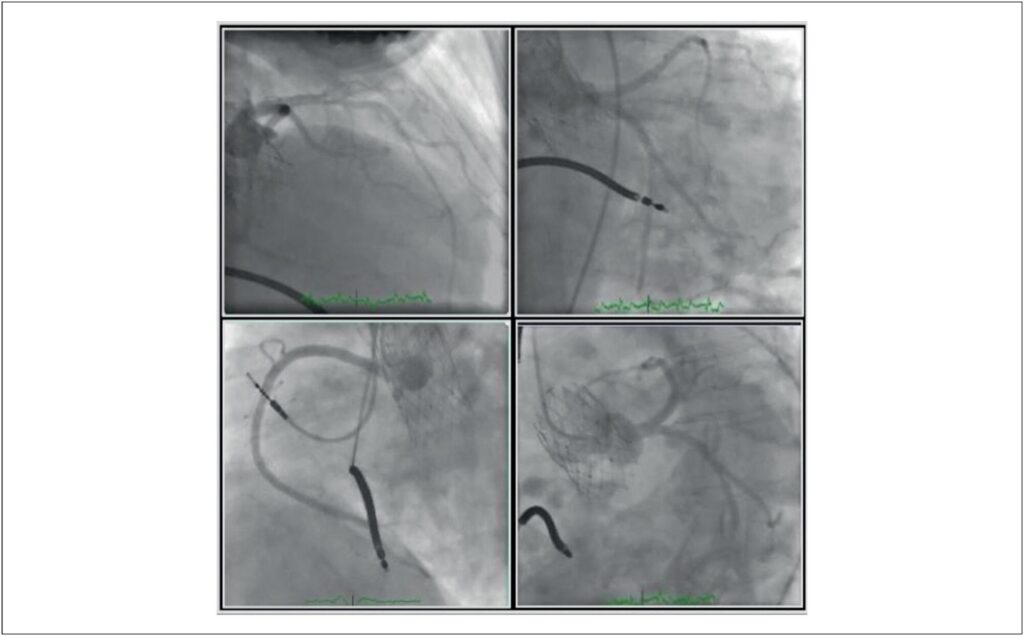

Evolução Tardia da Cardiomiopatia de Takotsubo Após Implante Transcateter de Valva Aórtica

O implante transcateter de valva aórtica (TAVI) é considerado uma opção terapêutica de primeira linha para pacientes sintomáticos que sofrem de estenose aórtica avançada e estão sob risco cirúrgico elevado. Em pacientes inoperáveis com prognóstico ruim, há risco de complicações, tais como infarto do miocárdio devido à oclusão coronária, acidente vascular cerebral, ruptura anular etc. A cardiomiopatia de Takotsubo (TTC) é uma síndrome que geralmente se desenvolve na ausência de oclusão coronária evidente e sinais de diagnóstico alternativo, incluindo miocardite. Apresenta-se com alterações eletrocardiográficas, aumento de biomarcadores cardíacos e achados ecocardiográficos típicos., Neste artigo, descrevemos uma paciente com TTC que havia sido previamente submetida ao TAVI e, posteriormente, ao implante de cardioversor-desfibrilador implantável (CDI).